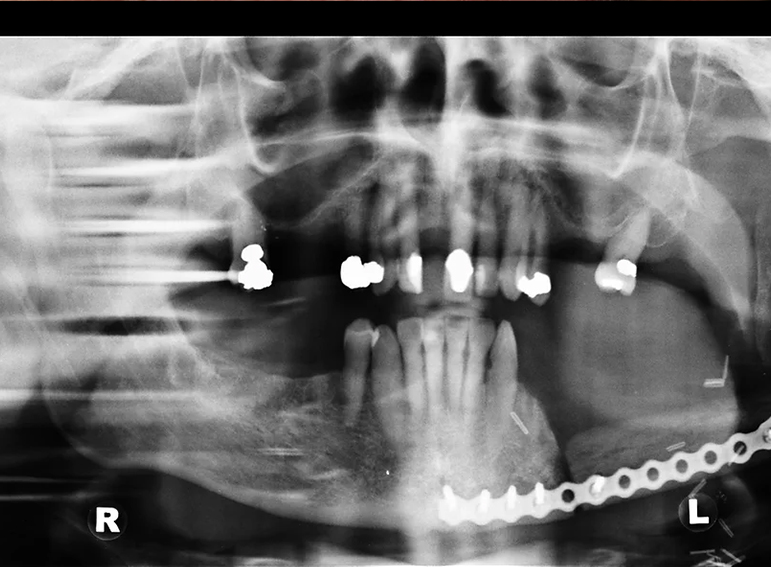

Complex upper and lower denture after oral cancer.